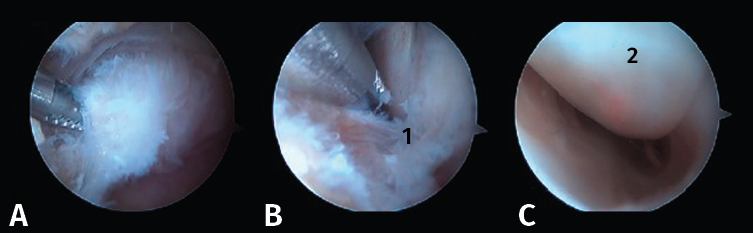

Figura 7. A: resección del ligamento astrágalo-calcáneo posterior (LACP) (1) en la parte inferior del proceso posterolateral del astrágalo (PPA); B: PPA (2) después de la resección completa de los ligamentos circundantes.

En ocasiones, está desprendido y se puede retirar fácilmente con una pinza grasper. Pero, si está fijado por fibrosis, es posible separarlo mediante el empleo de un desperiostizador o el sinoviotomo. Pero, cuando la fusión está calcificada, será preciso emplear un osteotomo de 5 mm introducido por el portal artroscópico. El fragmento escindido se extrae mediante una pinza grasper. También se puede utilizar un terminal de fresado para hacer la resección o para finalizarla regularizando los bordes del hueso. El límite del cartílago de la articulación subastragalina constituye el mejor punto de referencia para asegurarnos una resección adecuada (Figura 9).

Figura 9. Aspecto final después de la resección ósea. Se aprecia perfectamente el límite del cartílago de la articulación subastragalina.